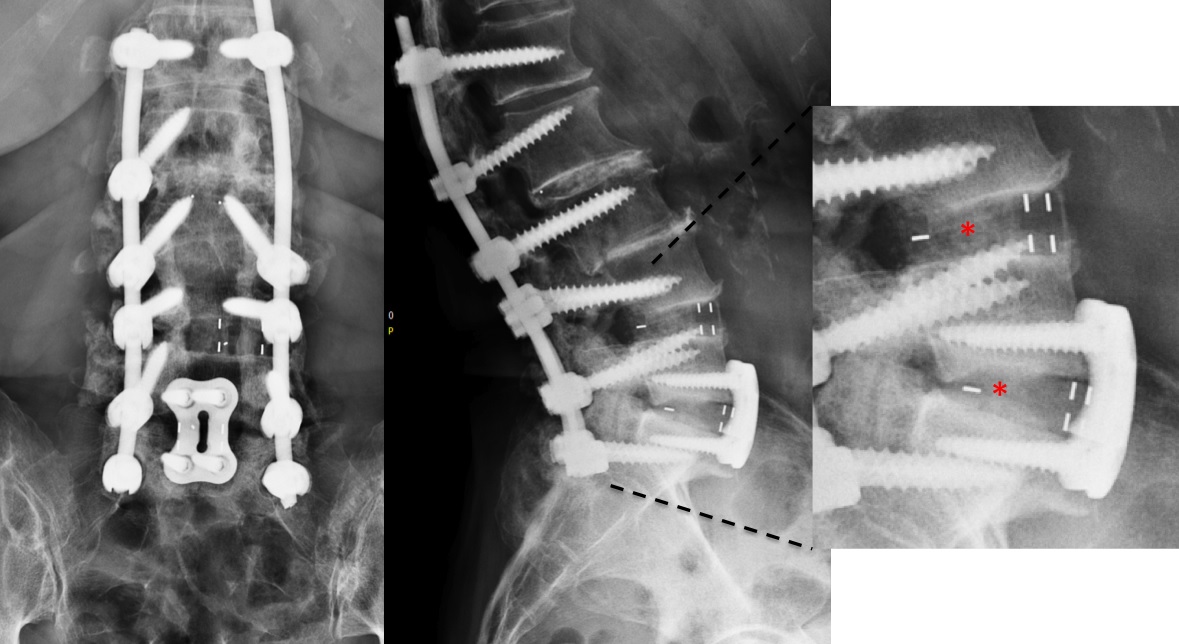

At level L5/S1, a large cage with an angulation of 14 was selected and for L4/L5, a large cage with an angulation of 10 was placed. In order to perform a fusion, the cages were each filled with 6 mg of BMPII.

From six months postoperatively, leg discomfort decreased. Within an additional four months, pain disappeared completely and both foot and hip weakness recovered. The back pain persists to a certain extent but is not impedingthe patient in her daily activities. The x-ray taken 10 months after the anterior revision surgery revealed a complete and solid fusion on both levels (Fig 8). This is confirmed by the appearance of dense bone in the radiolucentcage.